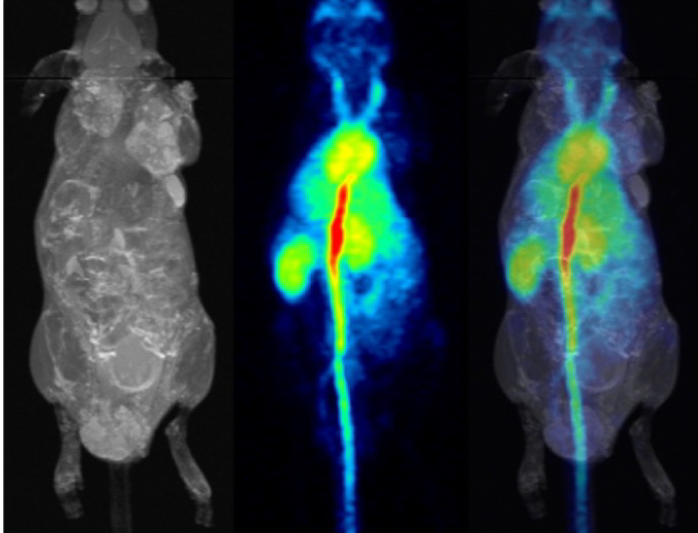

pmod’s tools provide comprehensive workflows for post-processing and quantification of imaging data for fundamental oncology research, development of radiotracers and theranostics, and in clinical research studies. Imaging scientists can trust pmod to reproducibly read their data, interpret the meta-data/units and help users calculate statistics such as SUV for their studies and publications.

Handle multimodality data and applications

For treatment evaluation and theranostic development